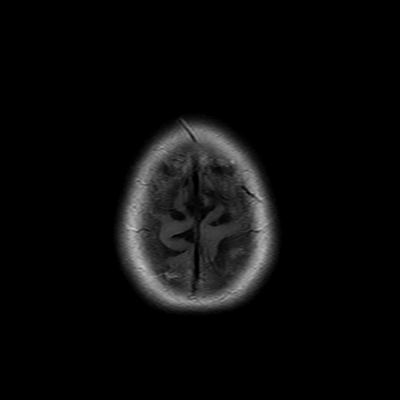

You also obtain an MRI of his brain once it's clinically safe to do so.

MRI brain (FLAIR)

You are now very concerned that he truly has an infectious meningoencephalitis.